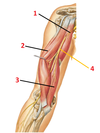

1? 2?

1: Levator scapulae muscle

2: Rhomboid major and minor muscles